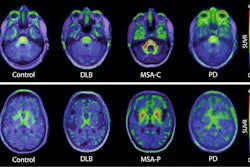

During a June 28 presentation, AC Immune research scientist Francesca Capotosti, PhD, will discuss the development of a PET tracer for the diagnosis of a‑synucleinopathies, which can help in the diagnosis of Parkinson's disease. The presentation will take place during a panel covering non-Alzheimer's neurodegenerative disorders at the conference.